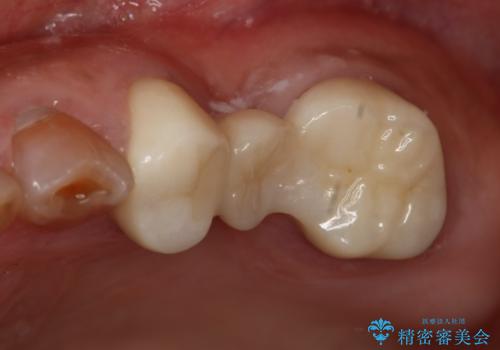

- 右下6番のメタルインレー脱離のため来院。

セラミックの治療を希望されたため切削量を考慮し、セラミックインレーでの治療を選択しました。

う蝕が深くまで進行していたので、CRで裏層した上で形成・印象をしています。